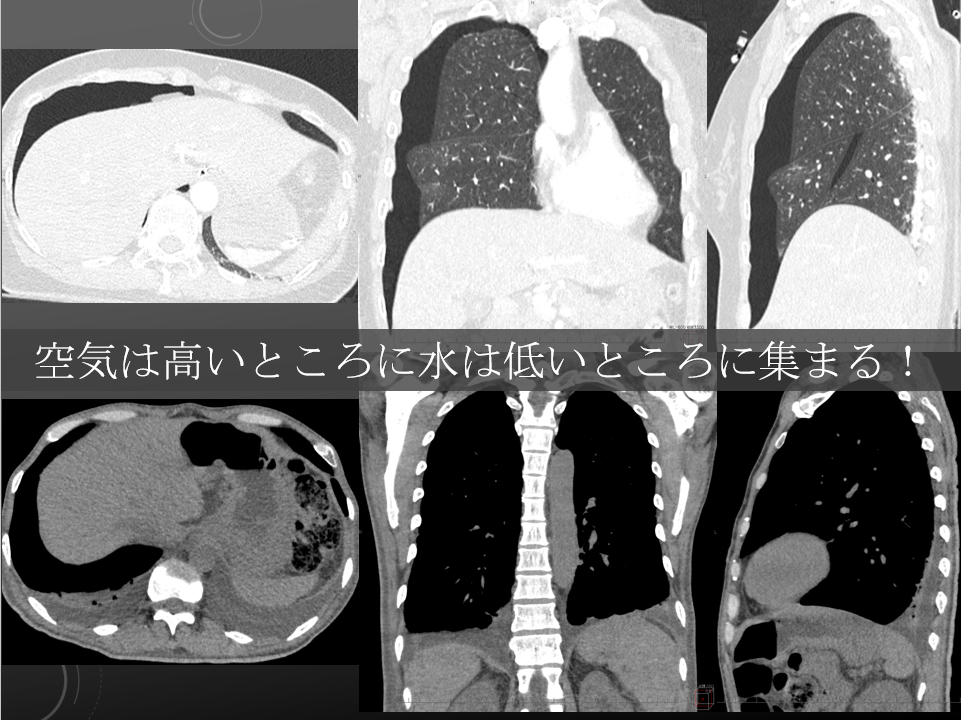

臥位と立位

臥位と立位